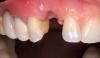

60-летний мужчина с симптомами адентии обратился за стоматологической помощью по поводу проблем пережёвывания пищи (фото 1 - 2). Пациент выявил желание восстановить имеющиеся дефекты при помощи несъёмных конструкций с опорой на дентальные имплантаты. В области нижней челюсти был обнаружен частичный дефект зубного ряда, а также собственные фронтальные зубы, которые не поддавались восстановлению (фото 3).

Фото 1. Вид до начала лечения.